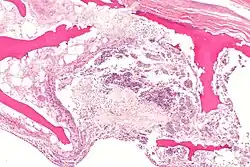

| X-ray of hip with femoral head osteonecrosis | |